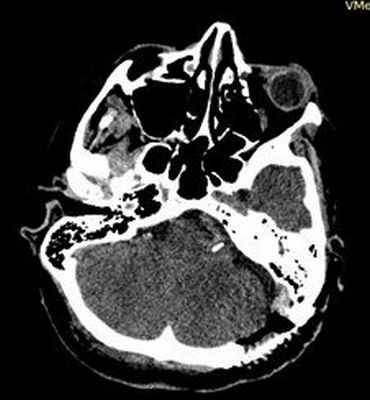

(Слева) При аксиальном исходном изображении (МРА) у пациента с спазмом правой половины лица визуализируются извитая правая позвоночная артерия и ЗНМА, воздействующие на область выхода корешка лицевого нерва. В цистерне мостомозжечкового угла (ММУ) визуализируется лицевой нерв.

(Справа) При аксиальной МРТ CISS на уровне цистерн ММУ у пациента с правосторонним гемифациальным спазмом определяется петля ЗНМА, смещающая ЧН VII в цистерне ММУ кзади, в результате чего он «свешивается» с заднего края слухового отверстия.

(Слева) При аксиальной МРТ CISS у пациента с левосторонним гемифациальным спазмом визуализируется петля левой позвоночной артерии, выдающаяся в цистерну ММУ, где она воздействует на проксимальную часть лицевого нерва в области выхода корешка.

(Справа) При аксиальной МРТ Т2 ВИ у пациента с гемифациальным спазмом определяется долихоэктазия позвоночной артерии, воздействующей на зону выхода корешка лицевого нерва во внутренних отделах цистерны ММУ. Приблизительно у 50% пациентов с гемифациальным спазмом обнаруживаются изменения на МРТ, обычно на тонкосрезовых Т2 последовательностях или МРА.